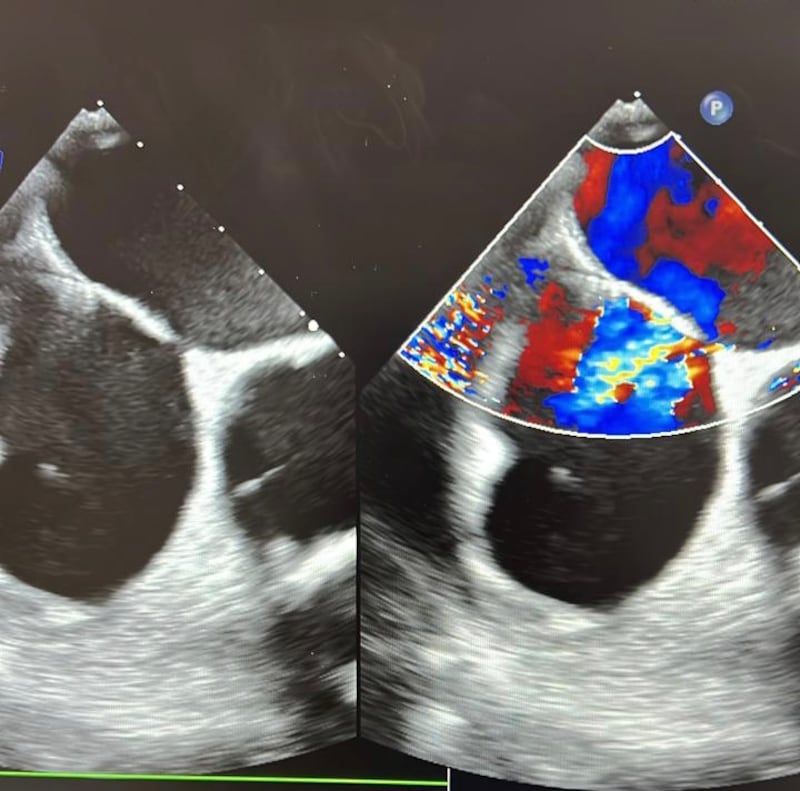

تمكن فريق طبي في مستشفى جامعة السلطان قابوس من إجراء عملية قسطرة ناجحة، لثقبين في الحاجز الأذيني لحالة مستعصية نادرة؛ عانى بسببها المريض من نزول حاد في مستوى الأوكسجين حالة الجلوس أو الوقوف ما يسمى ضيق النفس القيامي.

وقام الفريق -بقيادة كل من الدكتور فهد بن عبدالله الكندي طبيب استشاري أول في القسطرة التداخلية والهيكلية، والدكتور خلفان بن سالم السنيدي طبيب استشاري أول في القسطرة الهيكلية للأطفال- بإجراء العملية بنجاح وإغلاق الثقبين؛ ما أدى إلى تحسن مستوى الأوكسجين عند المريض من ٦٥ إلى ٩٠ بالمائة عند الجلوس.